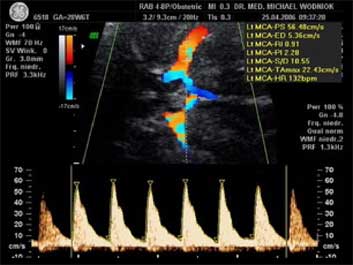

Unterscheidung zwischen dem anlagebedingt kleinen (nicht gefährdeten) und dem minderversorgten (gefährdeten) Kind. Der Nachweis einer chronischen Mangelversorgung des Kindes durch eine nicht ausreichende Funktion des Mutterkuchens (Plazenta) gelingt mit der Dopplersonographie durch die Messung der Blutströmungsverhältnisse in der Nabelschnurarterie und Gehirnarterie des Kindes mit de Dopplersonographie.

Zusammengefasst ist die Dopplersonographie ist eine Art Frühwarnsystem. Denn krankhafte Veränderungen beim CTG (Herztonaufzeichnung des Kindes) treten etwa erst 10-14 Tage nach den ersten Auffälligkeiten in der Dopplersonographie auf. Liegt ein Risiko gemäß den Mutterschaftsrichtlinien vor, wird die Doppleruntersuchung von uns zu Lasten der GKV abgerechnet.